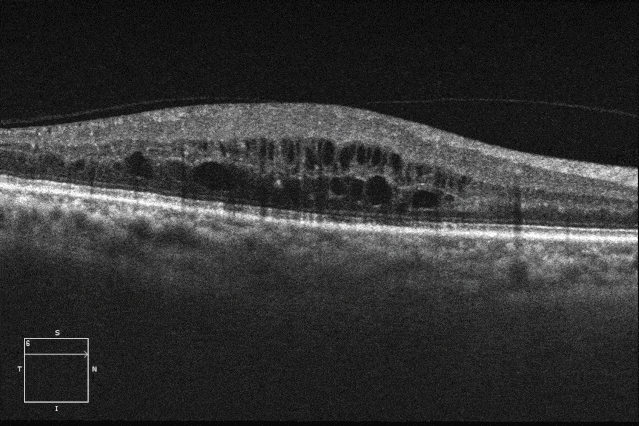

提示:双眼中周局部片状无灌注区,伴随散在激光斑覆盖

黄斑水肿明显,少许